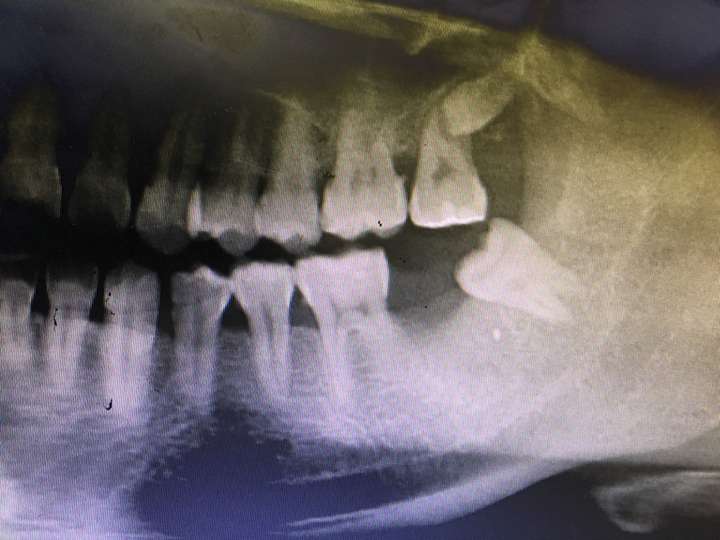

严重的拔牙并发症处理及病例示教|牙拔除术|牙槽窝|干槽症|神经管

▼图16-3在直视下对牙槽骨进行处理时,牙槽中间骨脊的垂直分类等级

拍片检查牙槽骨是否骨折或者咬合错乱,拔牙一个半月后再做牙槽骨修整